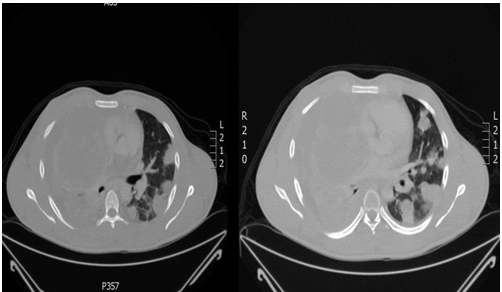

In our hospital, initially, this patient was admitted in the ICU because of severes hortness of breath, the review of CT done outside showed same finding that was mentioned in the report from outside hospital. Once the diagnosis was confirmed as choriocarcinoma (tumor cells were reactive to HCG and AE1/3 but negative for PLAP, CD30, CD117, AFP and Oct-4), the chemotherapy was started in form of VeIP protocol every 3 weeks as follows: Vinblastine(0.11 mg/kg IV in 50 ml NS over 15 minutes- day-1 and 2), Ifosfamide – (1500 mg/m2 IV in 500 ml D5 1/2 NS over 1 hour. Day 1–4 – with mesna), and Cisplatin (20 mg/m2 IV in 100 ml NS over 30 min – day 1–5). Our decision at hat time based on that we cannot start on BEP protocol, which contain Bleomycin/Etopside/cisplatin because of high risk of pulmonary toxicity with bleomycin, as this patient had an extensive lung disease and heavy smoker. After finishing cycle 1 of chemotherapy, he felt better with less oxygen dependent than before. Portable chest X-ray was done at that time and showed some improvement (Figure 2), so the patient discharged with G-CSF SQ injection daily for 5 days.The baseline β-hCG was 54.000 IU/ml with elevated LDH (574 units/L) and normal fetoprotein (2.12 ng/ml) (Table 1).

Figure 2: Chest X-ray after 1st cycle (anterior-posterior view).